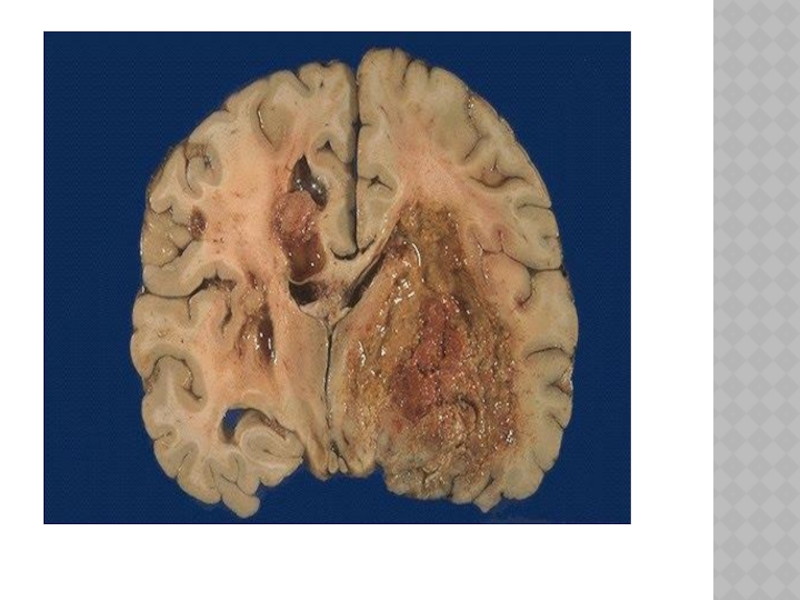

Слайд 131АБСЦЕСС ГОЛОВНОГО МОЗГА

Развивается при попадании микроорганизмов в мозговую ткань при открытом

ранении черепа, отите, пневмонии и других воспалительных процессах.

АБСЦЕСС ГОЛОВНОГО МОЗГАРазвивается при попадании микроорганизмов в мозговую ткань при открытом ранении черепа, отите, пневмонии и других

Слайд 132КЛИНИКА

протекают в две стадии:

1.Обнаруживаются симптомы, указывающие на наличие воспалительного

процесса (менингит, энцефалит), которые в процессе лечения уменьшаются или (реже) исчезают. 2.Мозговые симптомы, указывающие на внутричерепной объемный мозговой процесс+ признаки воспалительного процесса (лейкоцитоз в крови, ускоренное СОЭ, повышенное содержание белка и клеток в ликворе, повышение температуры).

КЛИНИКА протекают в две стадии: 1.Обнаруживаются симптомы, указывающие на наличие воспалительного процесса (менингит, энцефалит), которые в процессе

Слайд 133ДИАГНОСТИКА.

Анамнез, данные состава ликвора, компьютерная томография.

ДИАГНОСТИКА.Анамнез, данные состава ликвора, компьютерная томография.

Слайд 136ЛЕЧЕНИЕ

Хирургическое +антибиотики + сульфаниламиды

ЛЕЧЕНИЕХирургическое +антибиотики + сульфаниламиды